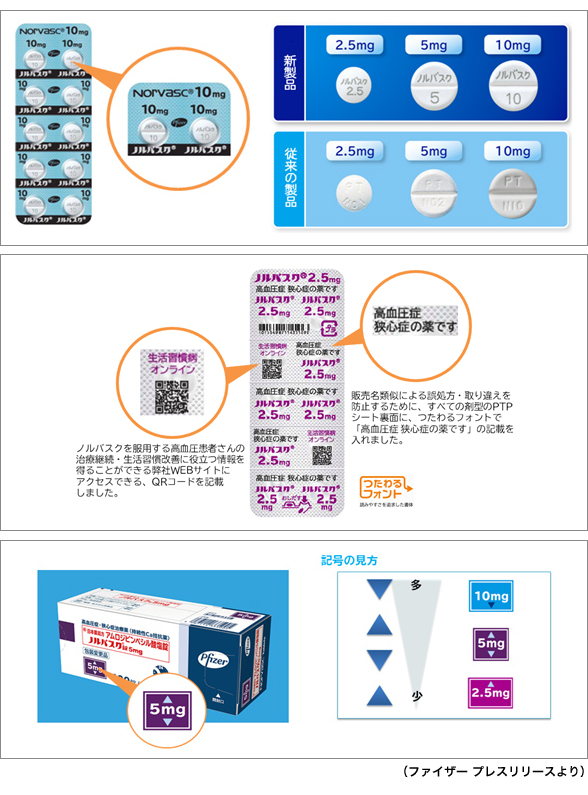

ptp包装シートの誤飲 平成23年4月 日本薬剤師会 Ppt Download

ptp包装シートの誤飲 平成23年4月 日本薬剤師会 Ppt Download

ptp包装シートの誤飲 平成23年4月 日本薬剤師会 Ppt Download

Ppt ptp包装シートの誤飲 Powerpoint Presentation Free